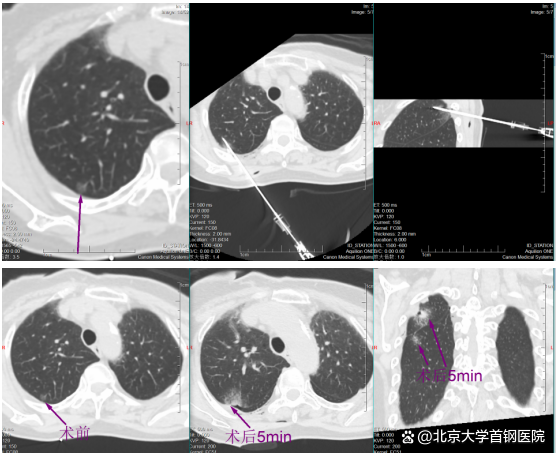

挑战随即开始。帕金森病导致黄女士身体不时微颤,这对需要毫米级稳定的穿刺是巨大干扰。于明川凝神屏息,双手稳如磐石,细微调整针道,在CT的实时引导下,消融针稳稳穿过8毫米的磨玻璃结节,精准停在胸膜前方3厘米处,完美避开胸膜危险区。“开始消融,30瓦一分钟!”随着指令下达,微波消融针开始加热,热量在结节处缓缓扩散,将病灶逐步凝固坏死。黄女士全程清醒,未感丝毫不适。

一分钟后,复查CT显示,结节被一圈磨玻璃密度影完整包裹,这意味着病灶已完全处于烧灼区内,第一枚结节消融成功!

image